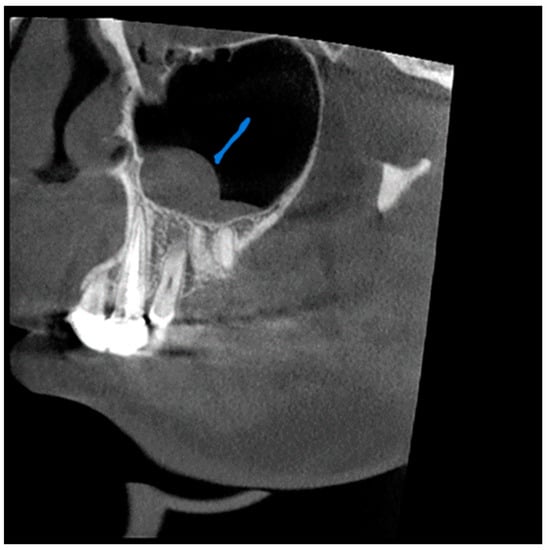

A total of 68 patients had pathologic findings in one or both sinuses, such as mucosal thickening, odontogenic cysts, fracture, hypoplasia, and bone lesions (58.1%) (Figure 1, Figure 2, Figure 3 and Figure 4). Of the 55 male patients, 33 had pathologies, like oroantral communication and inflammatory cysts in either sinus, whereas only 35 of the 62 scans of the female patients revealed radiographically abnormal findings in either sinus. The difference between the male and female patients was insignificant (Table 1).

Figure 1. View from the sagittal plane. The Blue arrow shows shows a thickening of the mucous boundaries of the maxillary sinuses.